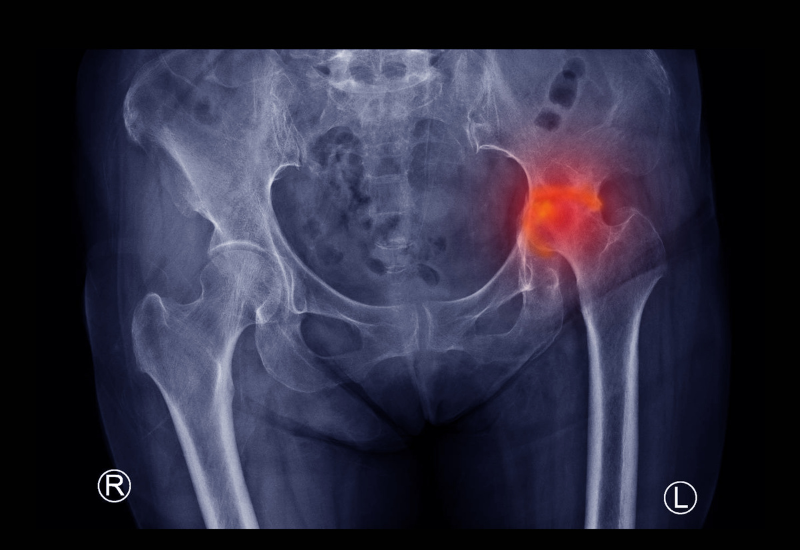

Avascular necrosis (AVN), also known as osteonecrosis, is a condition that occurs when there’s a loss of blood supply to a bone, leading to bone tissue death. This can cause pain, joint collapse, and disability. Stem cell therapy offers a potential approach to address AVN by promoting bone regeneration and blood vessel formation in the affected area.

If you’re struggling with pain, stiffness, and reduced mobility due to arthritis, you may benefit from our stem cell therapy options. Our therapies target various forms of arthritis, including osteoarthritis, rheumatoid arthritis, and psoriatic arthritis. Early research suggests that stem cells may have the potential to promote cartilage regeneration, reduce inflammation, and improve joint function.

Platelet Rich Plasma (PRP) Therapy involves extracting a patient’s own platelets and injecting them into injured tissues to stimulate healing. Widely used in sports medicine and orthopedics, PRP therapy accelerates recovery by enhancing the body’s natural repair processes, proving effective for tendon injuries, osteoarthritis, and muscle strains.

Injection Stem Cell Therapy is utilized for more localized issues such as joint degeneration or soft tissue damage. By injecting stem cells directly into the affected area, this therapy ensures that high concentrations of regenerative cells are delivered precisely where needed, enhancing the healing process and reducing recovery time.